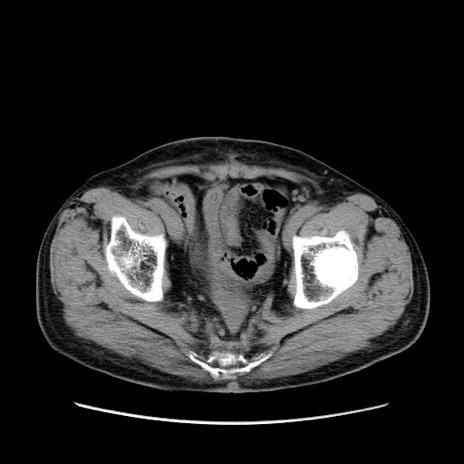

症例24(横断像)

【症例】80歳代男性

【主訴】左側腹部痛、嘔吐

【現病歴】本日早朝より左腹部に痛みあり。昼頃嘔吐認めたため、救急要請。

【既往歴】直腸癌(Mile手術)、胆摘

【身体所見】意識清明、BT 35.9℃、BP 221/93mmHg、SpO2 97%(RA) 、腹部:左ストーマ周囲に限局性の腹部膨隆あり。 膨隆部自発痛・圧痛あり・軟。

【データ】WBC 7700、CRP 0.09